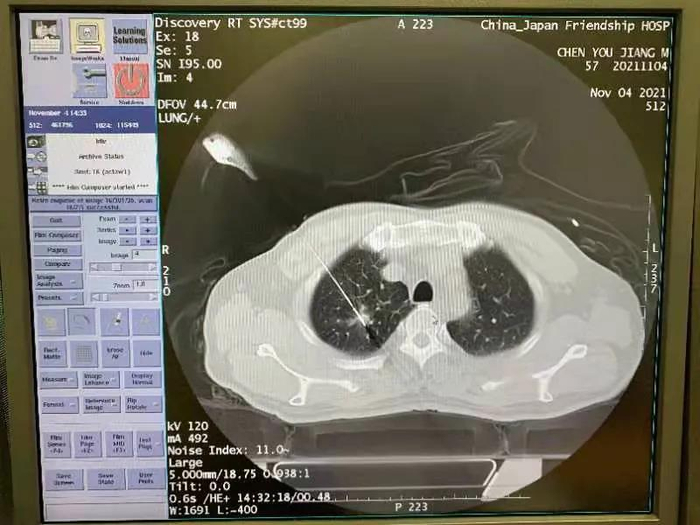

首例患者是一名57岁男性,两个月前出现咳嗽,少量咳血症状,查体发现右肺上叶有一处微小病灶。经多家医院影像学专家会诊,患者左肺下叶患有长期反复炎性病变,伴有左侧胸廓略塌陷,影像特征符合微小癌表现,双肺病变一侧考虑恶性。

为早日根除掉恶性病变,和患者沟通后,团队决定对右肺微小癌进行CT引导下经皮穿刺活检和消融治疗。

手术在介入医学科新建综合手术室进行,由于明安团队实施,手术麻醉科副主任张亚军给予术中支持。在一体化介入平台CT影像的清晰精确引导下,通过精准穿刺和多点布针,团队成功对右肺上叶肺癌病灶进行扩大消融,消融时间约20分钟。术后进行穿刺活检以备病理学检查,通过近24小时观察,患者平稳,没有出现气胸和出血等并发症,本次手术顺利完成。